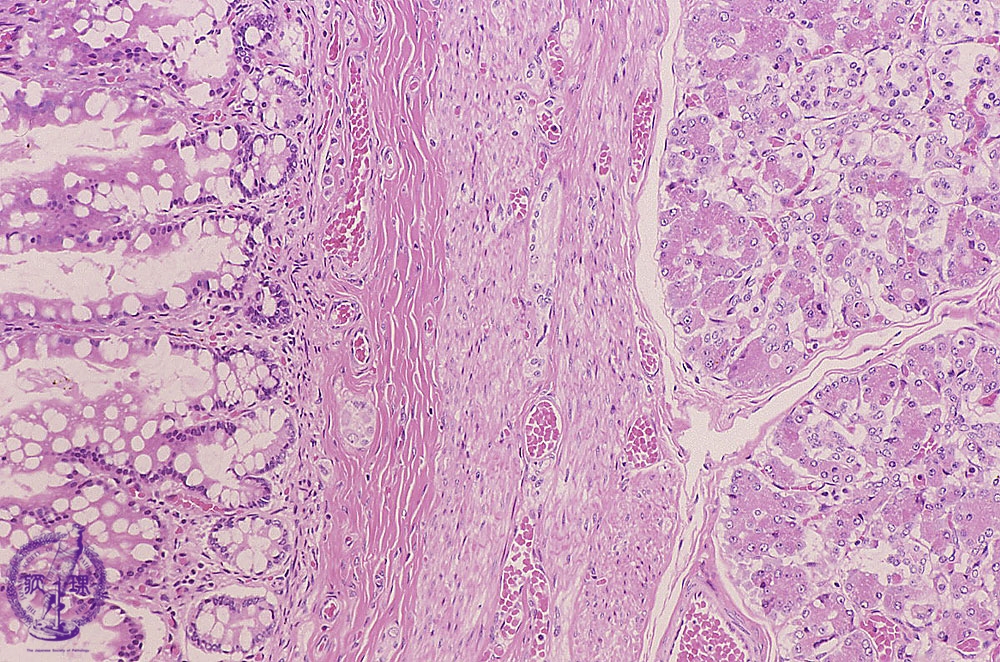

Microscopic view, high power; The inner lining is covered by mucosa resembling that of the small intestine with pancreatic tissue is present in the wall (arrow)